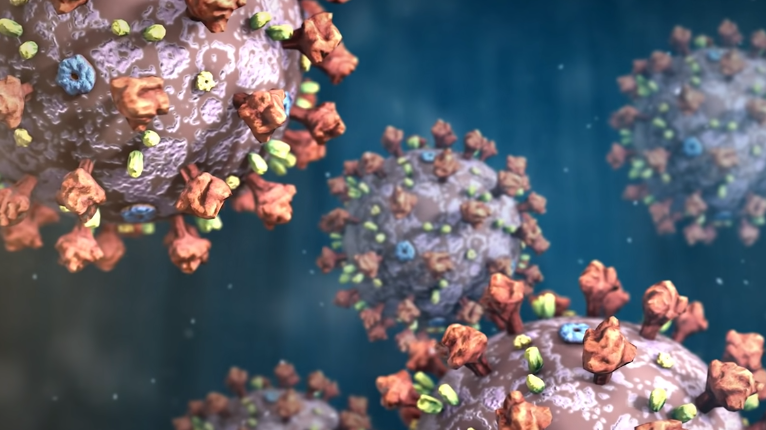

病毒身材呈圆形或椭圆形,直径约60-140nm,是一根头发丝的六百分之一。

为了更加直观的看它的结构,我们把它放大并给它的各个部分上个颜色。

可以看到在灰色的蛋白质外壳上均匀镶嵌着大量的冠状突起,这种独特的长相就是它叫冠状病毒的原因。

进一步我们剖开它的内部,一团紫色的线状物质映入眼帘,这是它所有的遗传物质 RNA,也是病毒赖以生存和繁殖的根本。

总的来说,病毒由一堆蛋白质组件和其内部的 RNA 构成。

其中,在冠状突起中最重要的一种蛋白叫做刺突糖蛋白(蓝色),这种蛋白可以识别人体细胞的表面ACE2蛋白(黄色)。举个例子,ACE2蛋白像一把锁,一般只有配对的钥匙才能打开它进入细胞内部。一颗合格的病毒会利用自己的技能合成出一把刺突糖蛋白仿制钥匙,堂而皇之的侵入细胞。这个过程就像这样: